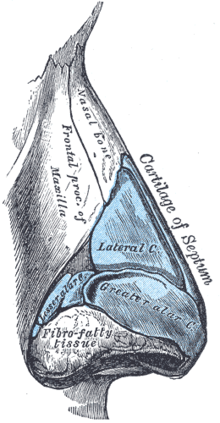

Nosní kost (latinsky: Os nasale) je párová kost, která je součástí lebky člověka. Má tvar obdélníku, její horní okraj se spojuje s pars nasalis čelní kosti (os frontale) a laterální okraj s processus frontalis maxillae. Přední plocha kosti je hladká a proděravěná několika otvůrky (foramina nasalis), kterými procházejí nervy a cévy. Na zadní straně je sulcus ethmoidalis, otisk od nervu, který tudy prochází. Vnitřní okraje nosových kostí tvoří šev (sutura internasalis). Svými vnitřními plochami přiléhají ke spina frontalis čelní kosti a lamina perpendicularis čichové kosti (os ethmoidale). Nosní kosti tvoří kostěný podklad nosu. U mužů bývá zahloubení „žlábku“ mezi čelní a nosní kostí větší, což je jeden z pohlavních rozdílů na lebce.